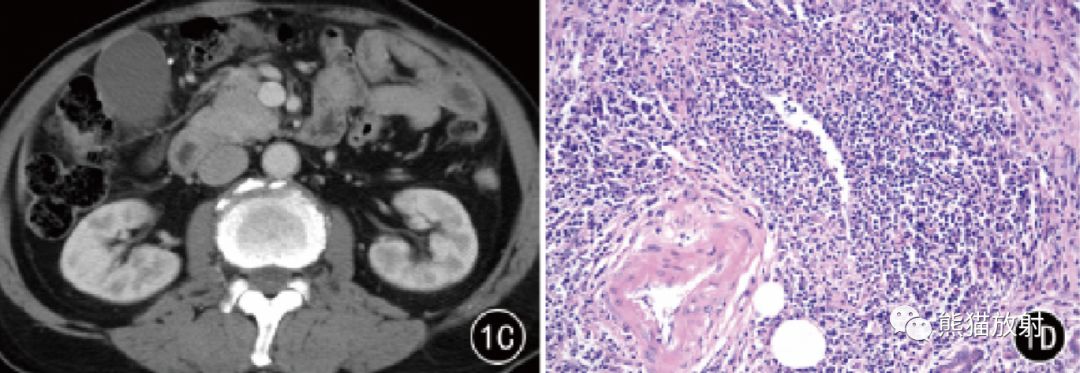

图1 男,75 岁。AIP 胰头部局灶性病变,CT平扫呈稍低密度,增强动脉期和门静脉期渐进性均匀强化。镜下见胰腺导管管壁增厚,周围炎性浸润和纤维化,闭塞性静脉炎( HE × 200)。